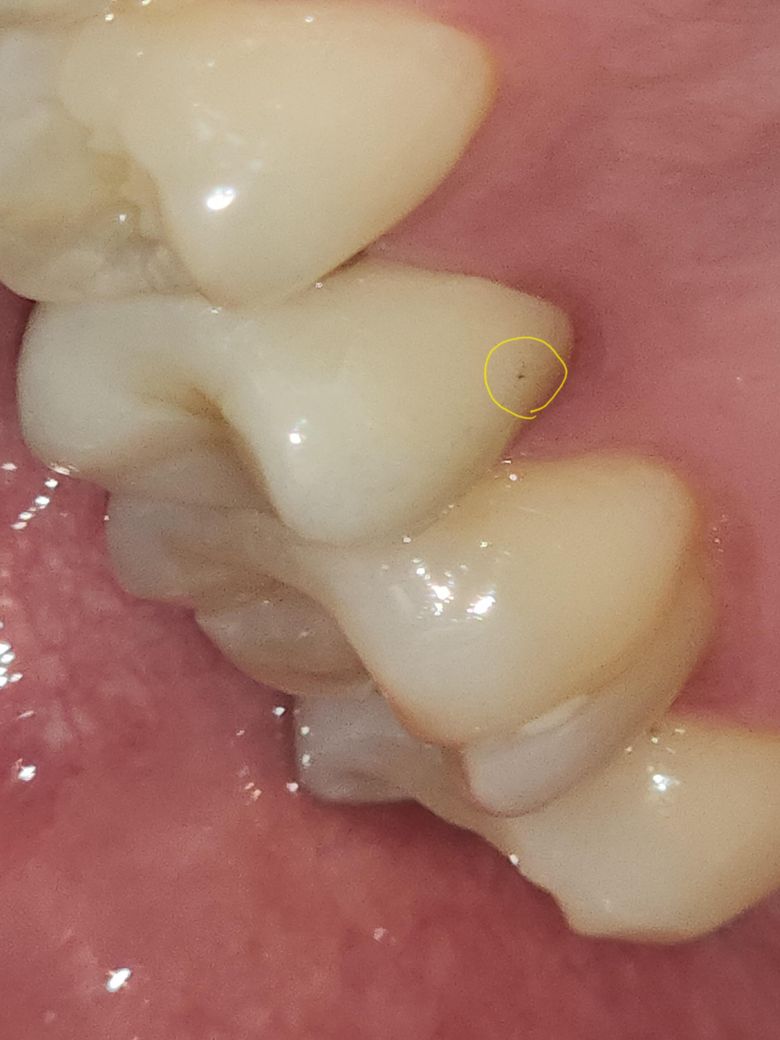

지르코니아 크라운의 검은점은 뭔가요???

제가 치아를 보던 중 지르코니아 보철 어금니에 검은점이 났습니다. 두번째 사진도 파랗게보이는 부분이 어금니고 보철치료했습니다.

이거 충치인가요?? 착색인가요?? 왜생신건가요?

보철물에 충치가 생기진 않고 보철물 표면에 착색이 발생한거같습니다. 치과에 가셔서 제거를 해달라고 하시면될것같습니다.

지르코니아 표면에는 검은색으로 보이는 물질이 있을 이유는 없습니다. 해당 부위를 폴리싱을 하다. 재료가 묻어 있거나 했을 가능성이 높습니다. 양치질을 꼼꼼히 해보시고 그래도 남아있다면 치과에서 제거를 해보는 것이 좋을 것으로 생각됩니다.

사진으로 보건데 보철물의 단순 착색으로 보입니다 스케일링,폴리싱 해보면 될 것 같습니다